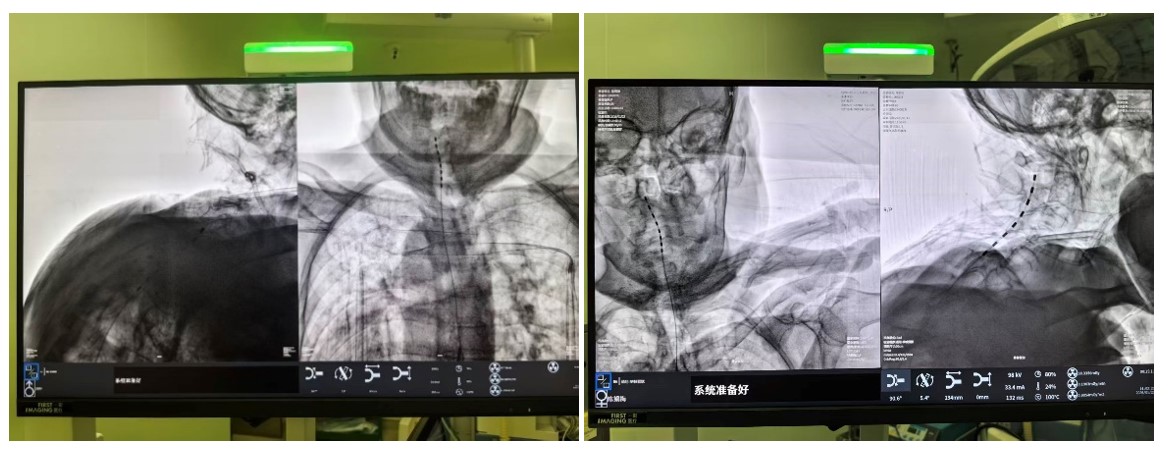

面对高龄且身体机能脆弱的患者,中南大学湘雅三医院疼痛科胡蓉教授团队经过严密评估,最终于1月中旬为两位老人实施了 “局麻下C臂引导下脊髓电刺激术(SCS)植入术” 。这项被称为神经调控领域“减痛黑科技”的技术,其原理在于:将微细电极植入脊髓硬膜外腔,通过发出微弱电脉冲,在疼痛信号传向大脑的路径上进行“精准拦截”,从而阻断痛感。

(C臂透视示术中电刺激已成功置入)

手术在局麻下进行,老人全程清醒。术中,当电极启动测试时,陈奶奶激动地反馈:“麻到了!颈根和肩胛都不痛了!”这种即时反馈确保了电极能够百分百覆盖痛区。术后一周,两位老人的疼痛视觉模拟评分(VAS,0分为无痛,10分为剧痛)从术前的8-9分骤降至2-3分,睡眠质量和情绪状态得到了质的改善。